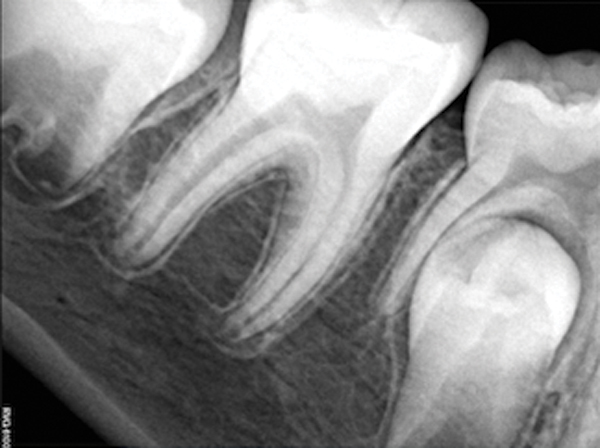

Figure 13. Tooth was asymptomatic at 1-year follow-up. Courtesy of Dr. Guillaume Jouanny.

Figure 13

Figure 14. Contralateral tooth at 1-year follow-up. Courtesy of Dr. Guillaume Jouanny.

Figure 14

In this case, the tooth tested vital but showed clinical signs of irreversible pulpitis. Treatment with a full pulpotomy was chosen to improve the chances the remaining pulp would survive and remain healthy. The preoperative radiograph in Figure 11 shows extensive caries in the tooth and a slightly widened apical periodontal ligament. A full pulpotomy was performed using the BC putty (Figure 12). After the putty set, a coronal restoration was placed, and an immediate postoperative radiograph was taken and viewed. At the 1-year follow-up, the tooth was asymptomatic, and the radiograph showed continued root development (Figure 13), a healthy apical periodontium, and, importantly, no calcifications in the remaining pulp (as is often seen with a calcium hydroxide therapy). A radiograph taken of the contra-lateral tooth showed similar root development (Figure 14).